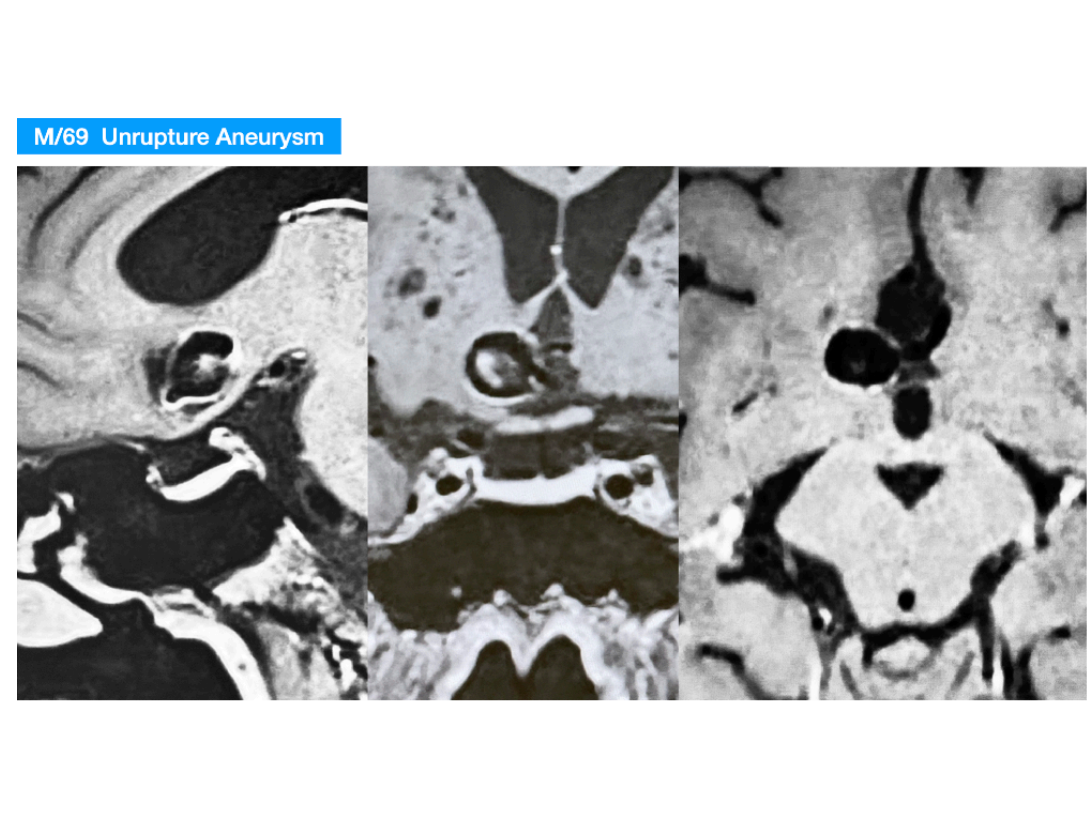

本期脑医汇为大家分享:天津市环湖医院【佟小光教授】的精彩病例内容:纵裂入路-前交通大动脉瘤夹闭术,欢迎阅读和分享!病例视频观看点击图片观看视频讲者:佟小光讲题:纵裂入路-前交通大动脉瘤夹闭术病例内容截图声明:脑医汇旗下神外资讯、神介资讯、神内资讯、脑医咨询、Ai Brain 所发表内容之知识产权为脑医汇及主办方、原作者等相关权利人所有。投稿邮箱:NAOYIHUI@163.com 未经许可,禁止进行转载、摘编、复制、裁切、录制等。经许可授权使用,亦须注明来源。欢迎转发、分享。